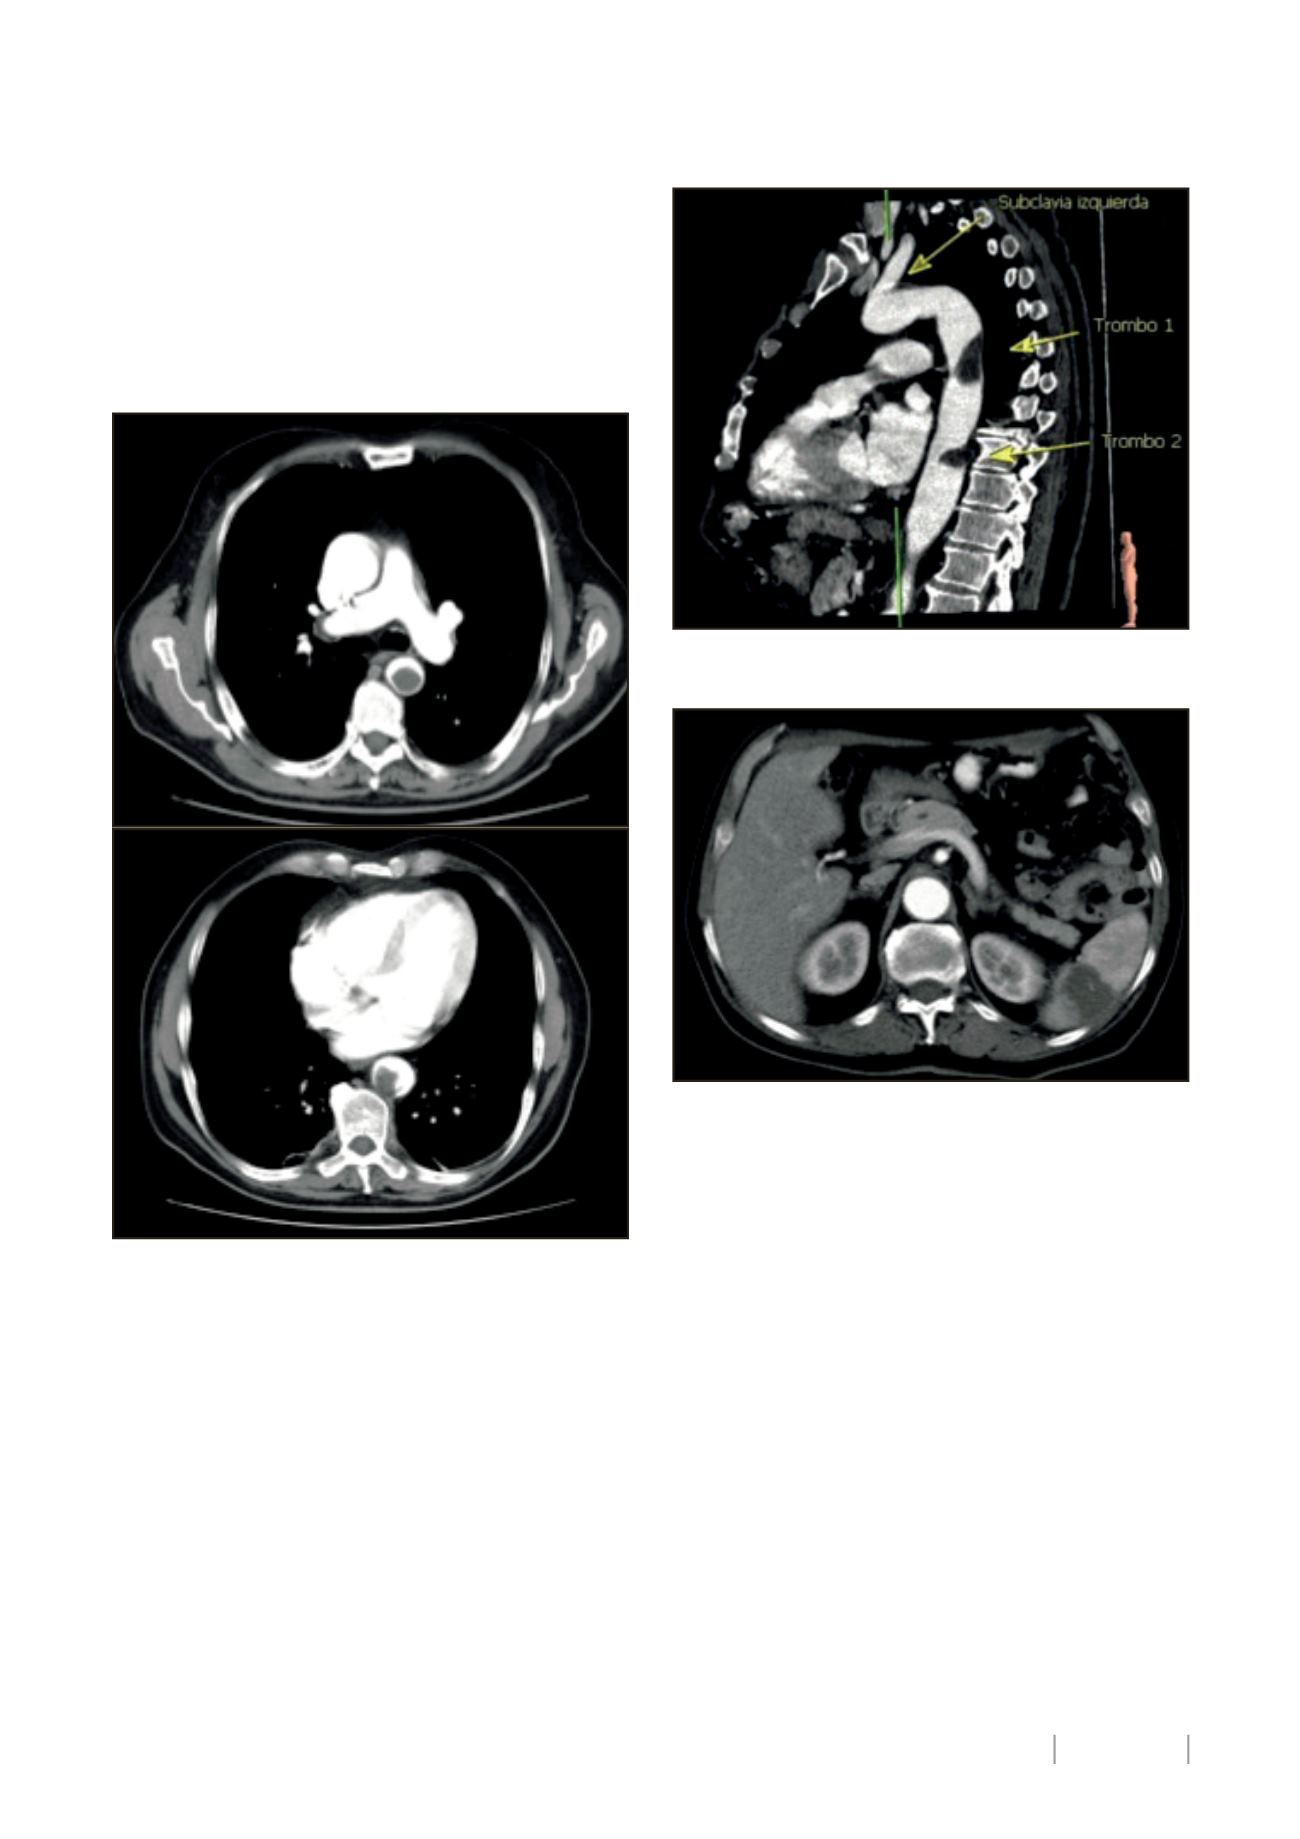

Posteriormente, 2 meses tras la cirugía, se realiza TC toraco-

abdominopélvico de control en el cual se observan:

• 2 trombos flotantes en aorta torácica descendente

(4x2cm + 3x2cm)

(Imagen 1 y 2).

• 3 nódulos hepáticos compatibles con metástasis

(<1cm).

• Infarto esplénico amplio

(Imagen 3).

Imagen 1 (a y b): Presencia de 2 trombos aórticos en AngioTC aorta

torácica.

Imagen 2: Reconstrucción de AngioTC con visualización de trombos

aórticos flotantes.

Imagen 3: : Infarto esplénico asociado a trombo flotante aórtico.